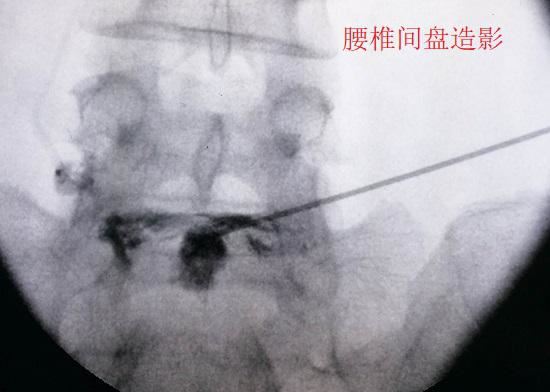

所谓轴性下腰痛,是指单纯的、且疼痛位置集中于腰椎附近的下腰背疼痛。轴性下腰背疼痛患者首先要进行至少6个月的保守治疗,在保守治疗无效的情况下,还可以考虑通过介入的方式对疼痛部位进行封闭治疗或阻断治疗。如果都没有效果且疼痛难以忍受,应通过影像学检查、椎间盘造影(以诱发疼痛)等手段进行诊断,在确定存在退变且疼痛部位与退变节段相关时,方考虑针对退变玛咖片的功效与作用节段实施融合手术。

腰椎间盘造影